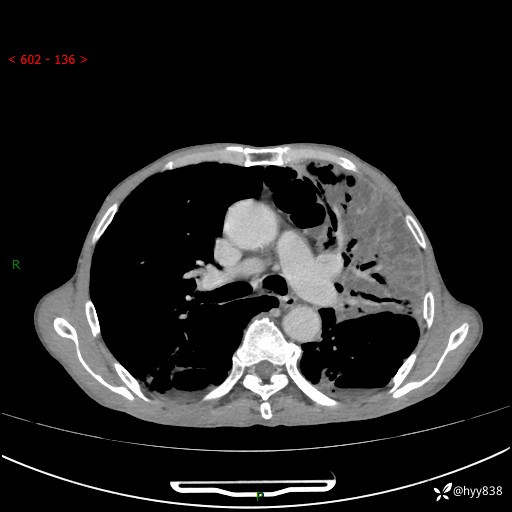

老年男性,反复咳嗽、咳痰、气喘10余年,再发3天。大叶性实变+胸膜病变-结果公布

胸部CT平扫+增强